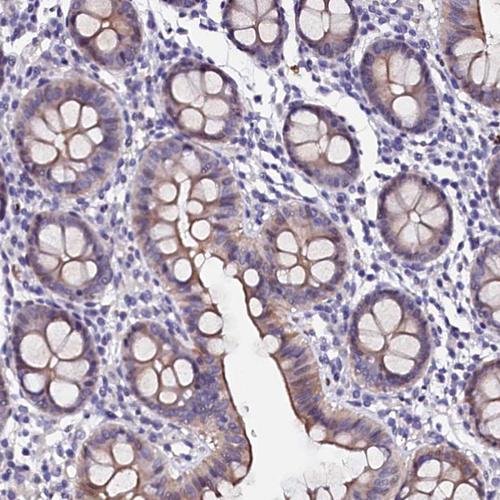

Immunohistochemical staining of human testis shows moderate nuclear/cytoplasmic positivity in Leydig cells.